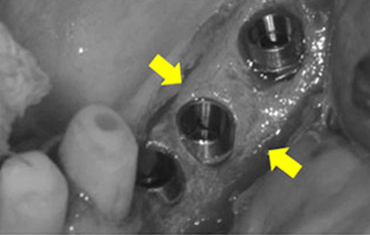

함몰 부위에 국소적으로 적용하는 간단한 방법의 뼈이식 임플란트

잇몸뼈가 찰 때까지 기다릴 필요 없이 즉시 식립과 동시에 뼈이식

임플란트 식립과 동시에 뼈이식을 하는 경우

폭이 많이 부족하여 뼈이식을 먼저 한 후, 임플란트 식립을 하는 경우